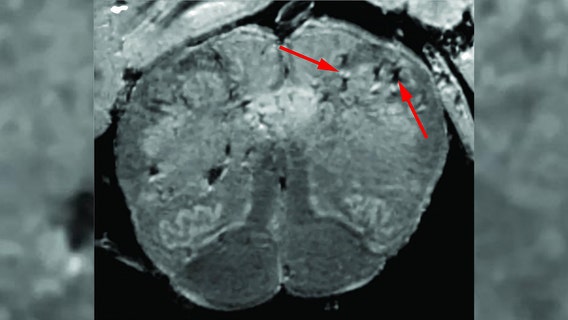

NIH launches online database to track, understand neurological symptoms associated with COVID-19